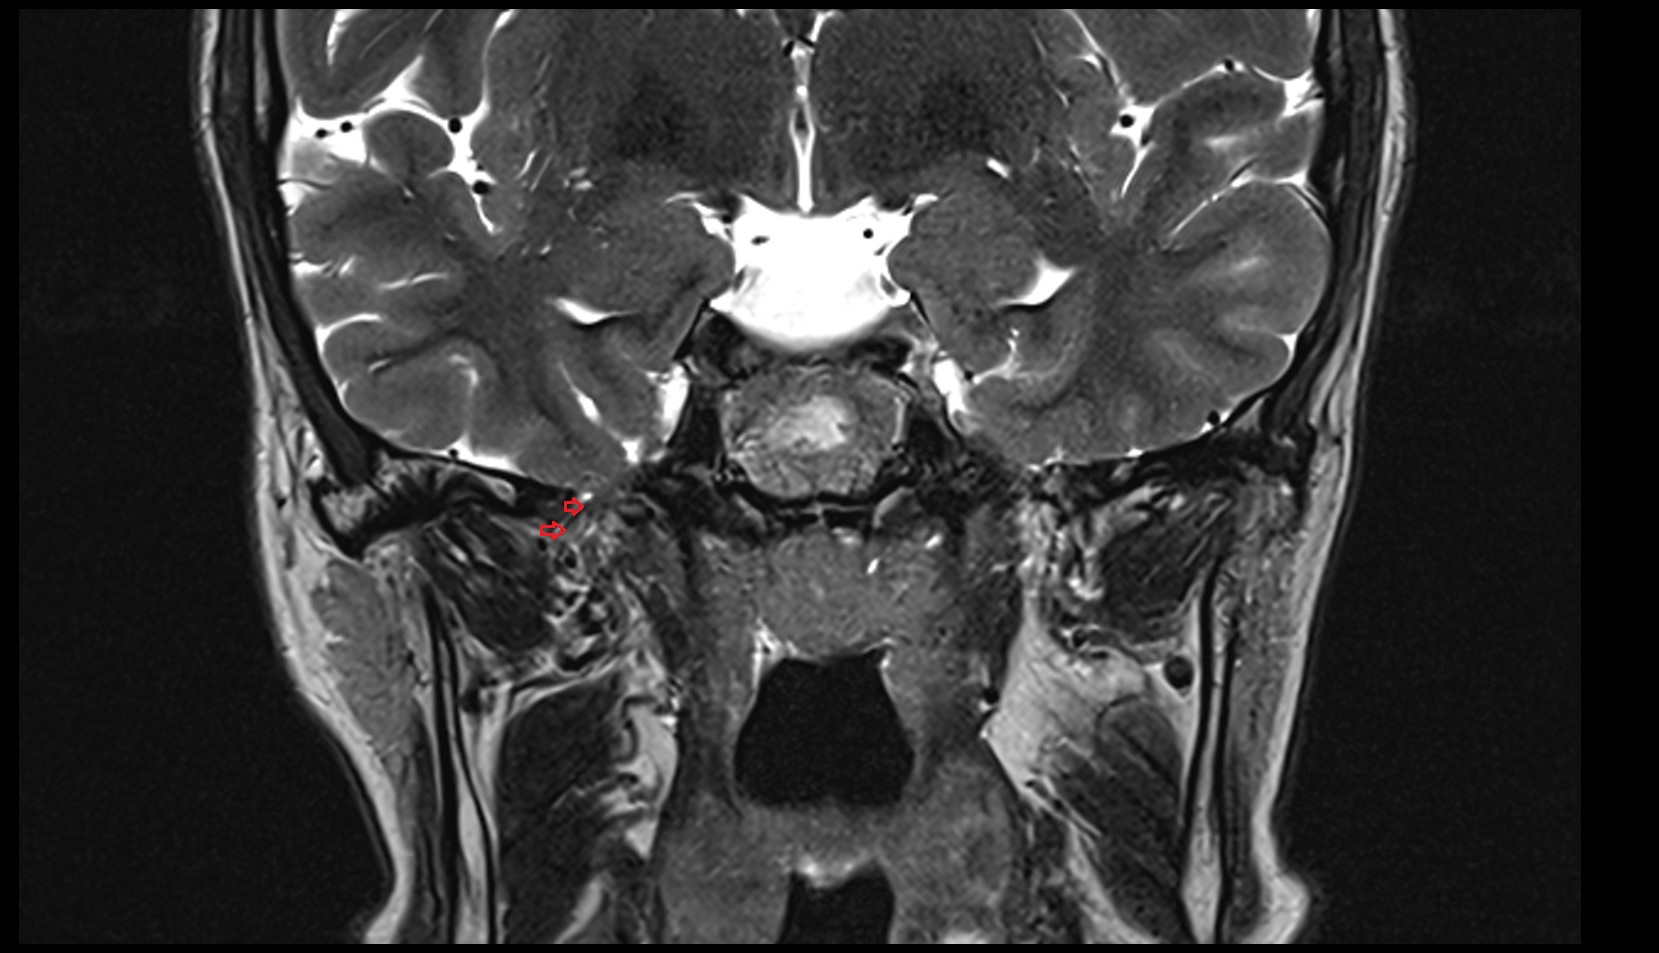

- Lateral aperture of fourth ventricle (foramen of Luschka)